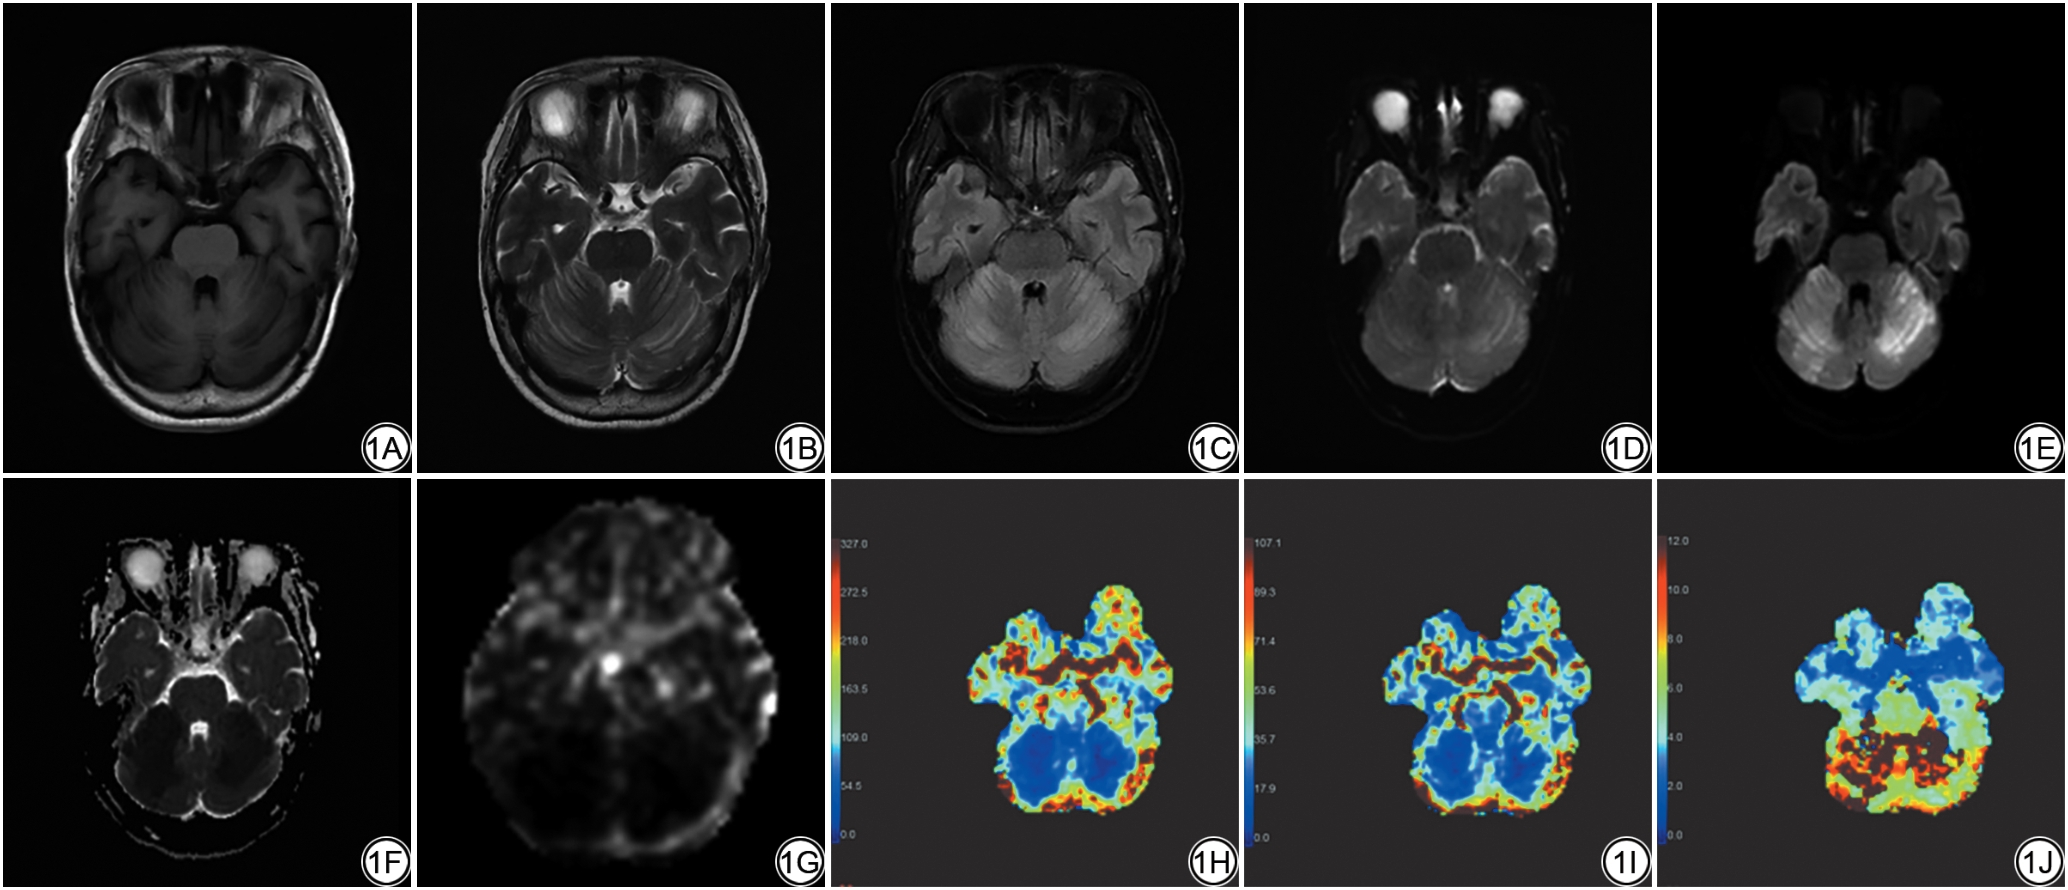

首先,确立金标准:由3名具有10年以上神经影像诊断经验的副主任医师独立勾画脑组织ROI(包括灰质、白质、病变区域),采用Delphi法(分歧率<5%时取均值,≥5%时重新评估)达成共识;随后,分别进行手动勾画及AI自动勾画。AI自动勾画结果与金标准的一致性通过以下指标评估:空间一致性采用Dice相似系数评估,体积测量一致性采用组内相关系数(intra-class correlation coefficient, ICC)评估;最后,基于ASL和DSC序列数据自动计算脑血流量(cerebral blood flow, CBF)、脑血容量(cerebral blood volume, CBV)参数(图1)。ROI放置规则:灰质置于额、顶叶正常灰质区(避开血管及脑室),白质置于半卵圆中心正常白质区,病变区域置于DWI高信号区最大层面,每个区域放置3个50 mm2的圆形ROI,取均值为最终参考值。

图1  女,69岁,AIS患者(PWI+AI组)。1A:T1WI;1B:T2WI;1C:FLAIR;1D:DWI-b0;1E:DWI-b1000;1F:DWI-ADC;1G:ASL-CBF;1H:DSC-CBF;1I:DSC-CBV;1J:DSC-Tmax;1K:MRA-MIP-颅脑;1L:MRA-MIP-头颈;1M:AI-Mismatch。1A~1C:T1WI、T2WI及FLAIR图示两侧小脑半球片状、斑片状异常信号,T1WI呈稍低信号,T2WI及FLAIR呈稍高信号;1D~1F:DWI(b=0、1000 s/mm2)及ADC图示扩散受限;1G~1J:PWI(ASL-CBF、DSC-CBF、DSC-CBV、DSC-Tmax)图示两侧大脑后动脉供血区大片状异常灌注区,ASL示CBF下降,DSC示CBF及CBV均下降;1K~1L:MRA包括MRA-MIP-颅脑及MRA-MIP-头颈,示两侧大脑后动脉P1段及椎动脉V4段严重狭窄;1M:AI-Mismatch图,示脑实质Tmax>6 s体积为100.7 mL,ADC<620×10-6 mm2/s体积为66.1 mL,缺血半暗带体积为34.6 mL,不匹配率约1.5。AIS:急性缺血性脑卒中;T1WI:T1加权成像;T2WI:T2加权成像;FLAIR:液体衰减反转恢复序列;DWI:弥散加权成像;ADC:表观弥散系数;PWI:灌注加权成像;ASL:动脉自旋标记;CBF:脑血流量;DSC:动态磁敏感对比增强成像;CBV:脑血容量;MRA:磁共振血管成像;MIP:最大密度投影;Tmax:达峰时间;AI-Mismatch:人工智能辅助缺血半暗带不匹配分析。

Fig. 1  A 69-year-old female AIS (PWI+AI group). 1A to 1C: T1WI, T2WI, and FLAIR images show patchy abnormal signals in both cerebellar hemispheres, appearing slightly hypointense on T1WI and slightly hyperintense on T2WI and FLAIR. 1D to 1F: DWI (b=0, 1000 s/mm²) and the corresponding ADC map demonstrate restricted diffusion. 1G to 1J: PWI maps, including ASL-CBF, DSC-CBF, DSC-CBV, and DSC-Tmax, reveal extensive areas of abnormal perfusion in the bilateral posterior cerebral artery territories; ASL shows decreased CBF, while DSC shows decreases in both CBF and CBV. 1Kto 1L: MRA, including MIP images of the cranium and head-neck, demonstrates severe stenosis in the P1 segment of both posterior cerebral arteries and the V4 segment of the vertebral arteries. 1M: An AI-Mismatch map quantifies the following volumes: Tmax > 6 s is 100.7 mL, ADC < 620 ×10-6 mm2/s is 66.1 mL, and ischemic penumbra is 34.6 mL, yielding a mismatch ratio of approximately 1.5. AIS: acute ischemic stroke; T1WI: T1-weighted imaging; T2WI: T2-weighted imaging; FLAIR: fluid-attenuated inversion recovery; DWI: diffusion-weighted imaging; ADC: apparent diffusion coefficient; PWI: perfusion-weighted imaging; ASL: arterial spin labeling imaging; CBF: cerebral blood flow; DSC: dynamic susceptibility contrast; CBV: cerebral blood volume; MRA: magnetic resonance angiography; MIP: maximum intensity projection; Tmax: time to maximum; AI-Mismatch: artificial intelligence-assisted ischemic penumbra mismatch analysis.